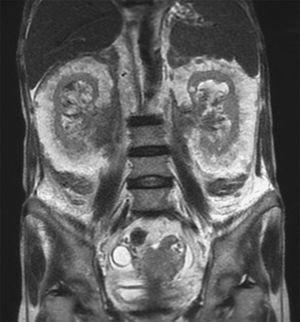

A 69-year-old woman with chronic kidney disease and myelofibrosis presented with a 2-day history of dyspnea and general weakness. Magnetic resonance imaging of the abdomen is shown here. What is the diagnosis? a) Renal-cell carcinoma b) Amyloidosis c) Angiomylipoma d) Perirenal extramedullary hematopoiesis e) Liposarcoma Source: nejm.org